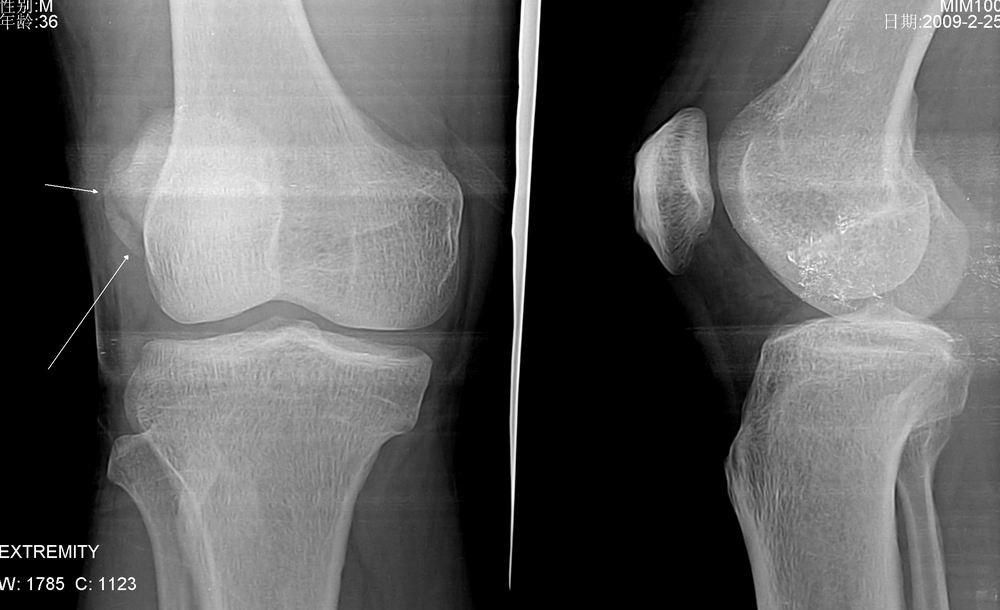

外伤就诊 醉了 不配合 体位照的不好

髌骨近外侧缘骨折。

——轴位投照值得俺学习。

正侧位体位好的话,不一定显示。

髌骨外侧缘骨折,照得不错,如无轴位可造成误诊。